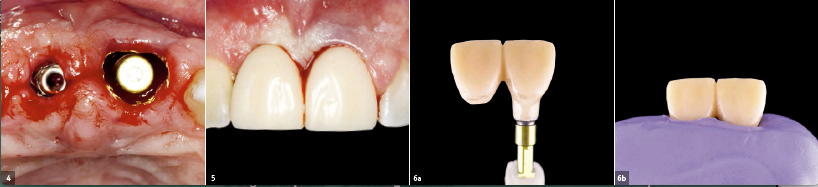

Εικ. 4

Το δεύτερο εμφύτευμα τοποθετήθηκε αμέσως μετά την εξαγωγή του 21.

Εικ. 5

Η προσωρινή γέφυρα με το γεφύρωμα στον 21 κοχλιώθηκε στο εμφύτευμα στην περιοχή του 11. Μετά από δύο μήνες, η παρειακή μορφολογία στην περιοχή του 21 διορθώθηκε με μόσχευμα συνδετικού ιστού.

Εικ. 6a&b

Κατασκευή του εξατομικευμένου άξονα αποτύπωσης για το εμφύτευμα στην περιοχή του 11. Το προφίλ ανάδυσης της προσωρινής αποκατάστασης θα πρέπει να μεταφερθεί στη μόνιμη αποκατάσταση. Αυτή η διαδικασία προλαμβάνει την κατάρρευση του προφίλ ανάδυσης κατά τη λήψη αποτυπώματος.